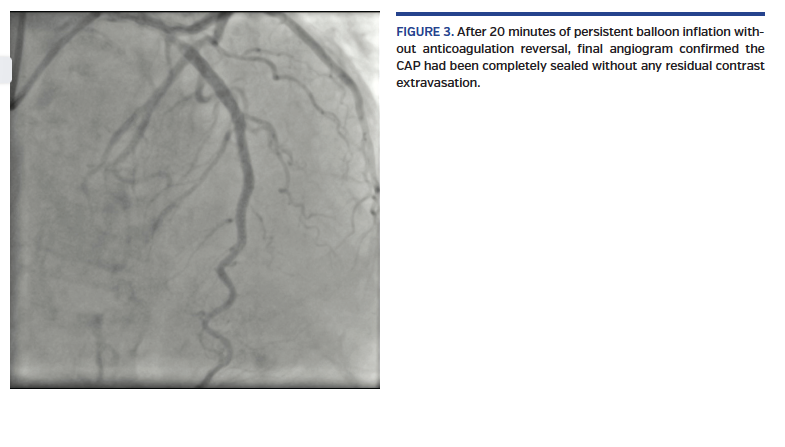

A short, 81-year-old woman presented with non-ST elevation acute myocardial infarction complicated with acute pulmonary edema. She was referred to urgent coronary angiography, performed via right distal transradial access, which is our default approach. The culprit left anterior descending (LAD) coronary artery was shown to have a long, tight, and calcified proximal-mid stenosis (Figure 1; Video 1), which was fixed by PCI with two drug-eluting stents (3 x 33 mm and 3.5 x 33 mm), requiring adequate pre- and postdilations with non-compliant balloons (2.5 x 20 mm and 3.5 x 20 mm, respectively). Surprisingly, the final angiogram showed an unexpected huge cavity spilling in-stent mid LAD perforation, with drainage to the left ventricle (Figure 2; Video 2). Promptly, the same postdilation NC 3.5 x 20 mm balloon was reinflated to 8 atm at the level of the CAP. After 10 minutes, there was some resolution. After a total 20 minutes of persistent balloon inflation without anticoagulation reversal, a final angiogram confirmed the CAP had been completely sealed without any residual contrast extravasation (Figure 3; Video 3). Transthoracic echocardiogram discharged pericardial effusion.